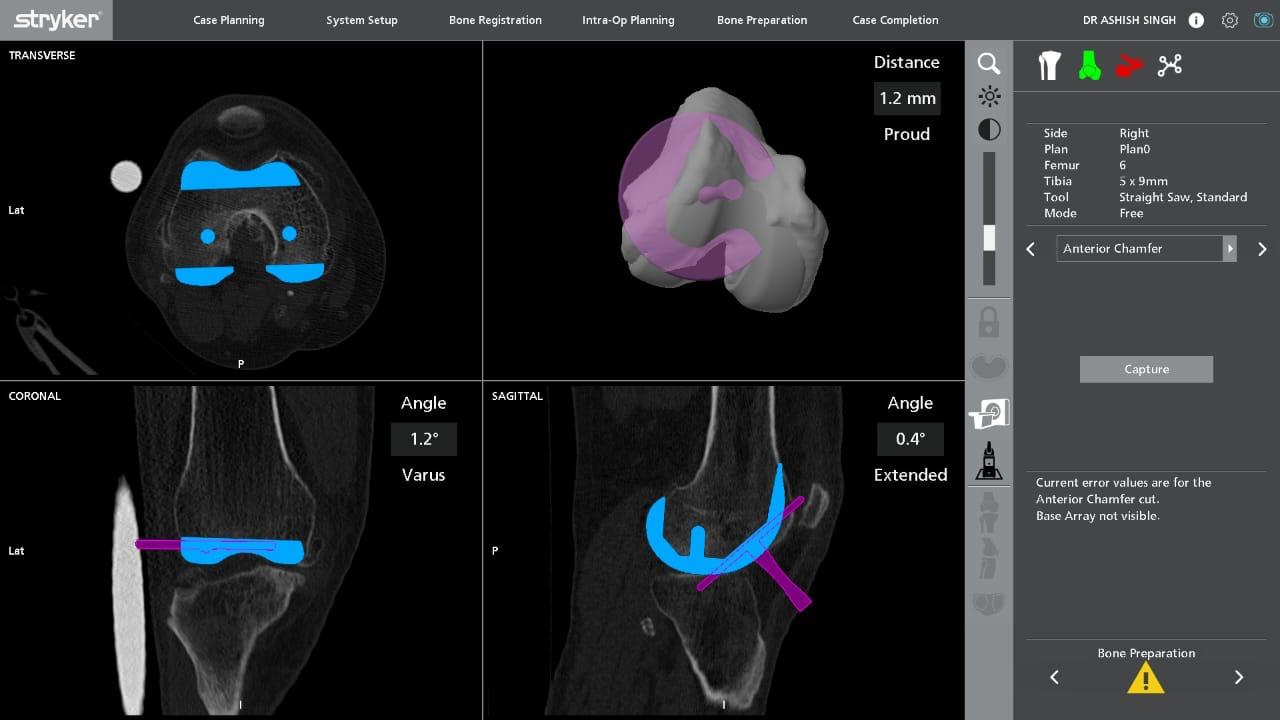

Assessment of Bone Resection Accuracy in Robotic-Arm-Assisted Total Knee Arthroplasty: A Prospective Observational Study

Akash Chandrashekar Gundalli , Ashish Singh , Purushotam Kumar , Kanukuntla Kalyan , Sudhir Shankar Mane , Himanshu Swarnkar

………………………………p.335-341